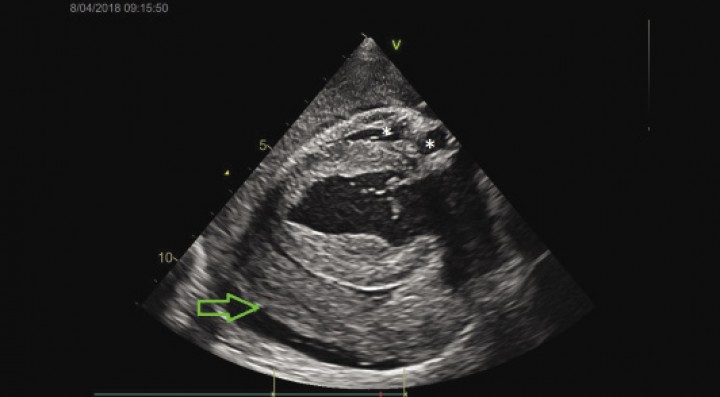

A los pocos minutos de iniciar el examen ecocardiográfico se observó un aumento difuso de la ecogenicidad en el derrame pericárdico con un colapso marcado de la aurícula y el ventrículo derecho y una reducción del volumen del atrio y el ventrículo izquierdo (Fig. 4). Estos hallazgos fueron compatibles con una rotura aguda de la aurícula izquierda con taponamiento cardiaco secundario a la dilatación de la misma por enfermedad degenerativa de la válvula mitral.

<p>Imagen ecocardiográfica: eje largo paraesternal derecho. La flecha verde señala el coágulo de grandes dimensiones y los asteriscos, el colapso de la aurícula y el ventrículo derecho.</p>

Imagen ecocardiográfica: eje largo paraesternal derecho. La flecha verde señala el coágulo de grandes dimensiones y los asteriscos, el colapso de la aurícula y el ventrículo derecho.